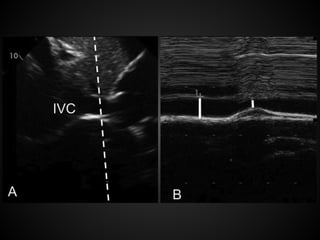

Volume Status

Diagnostic of hypovolemia in hypotensive

patients: empty heart or flat IVC

In hypovolemia, the ventricular walls will

come together or ‘‘kiss,’’ or in cardiologist

lingo, an ejection fraction >70%

Flat IVC: IVC collapses >50% during the

respiratory cycle

The Significance of the IVC

in Volume Status

The overall size of the vessel is not as

important as the variability.

Increasing the intra-thoracic pressure

would result on an increased IVC size but

might not change the variability. A small

IVC on a hypotensive ventilated patient is

diagnostic of hypovolemia, but a full IVC

does not rule out this diagnosis.